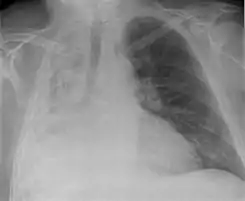

Atelectasia completa del pulmón derecho

• Radiografía del tórax: Detecta los siguientes signos radiológicos:

Signos Directos:

1. Retracción de las cisuras lobares.

2. Radiopacidad homogénea del lado de la lesión.

3. Acercamiento broncovascular.

Signos Indirectos:

1. Retracción del Mediastino hacia el lado de la lesión.

2. Elevación del hemidiafragma.

3. Disminución de los espacios intercostales.

4. Enfisema compensador( Hiperinsunflación).

5. Desplazamiento del hilio hacia el lado de la lesión.

6. Aproximación de las costillas.

En el adulto previamente sano que presente una atelectasia hay que sospechar una neoplasia que obstruye el bronquio. La presencia de todos los signos directos más la mayoría o todos los indirectos confirman la atelectasia.